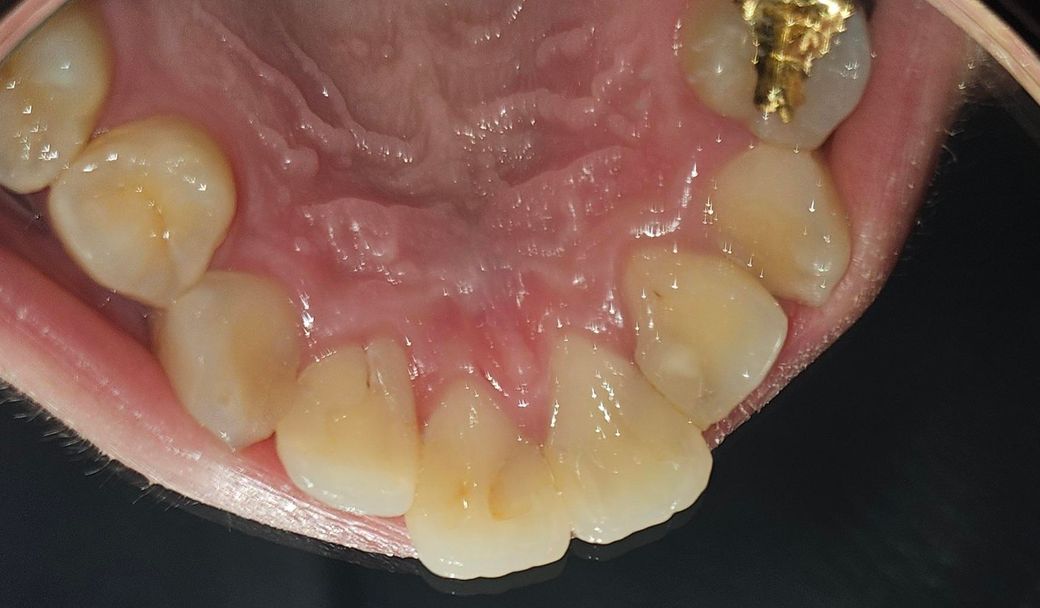

대문니 옆 작은대문니 뒤쪽 까만점 충치인가요?

통증도 따로 없구요. 그런데 오늘 보니 양옆 작은대문니 뒤쪽? 뿌리쪽에 까만점이 보이는데 이거 충치인가요? 낮에만해도 안보였던 것 같은데 갑자기 보이네요

대문니와 양쪽대문니등에 충치가 있는건지 궁금합니다.

• 2번 째 사진

확실하지는 않지만 충치의 가능성이 있어보입니다. 치과 가셔서 확인해보시는 게 좋겠습니다.

가운데 치아는 예전에 치료한게 약간 변색이된거 같고 옆에 치아는 조그맣게 충치가 잇는거 같습니다 .

충치라고 보기에는 그런 양상은 아니고 단순 착색, 변색으로 보입니다 치료가 필요한 정도 아닙니다

초기 충치의 가능성이 있어 보입니다. 우선 진행하지 않도록 꼼꼼히 양치를 하여 관리하고, 빠른시일내에 치과에 방문하여 상태를 확인후 치료여부를 결정하길 권합니다.